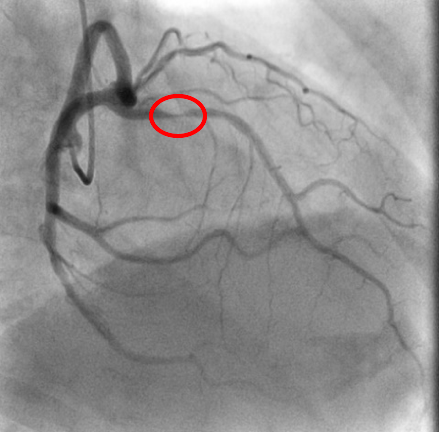

血管撮影とは

血管撮影装置では血管造影(アンギオ検査)を行います。 血管造影とは手首や足の付け根の動脈からカテーテルと呼ばれる細い管を血管の中へ挿入し、目的の位置(血管)まで移動させて血管を造影し、治療を行う検査のことです。

検査内容

主に循環器領域の冠動脈形成術(PCI)、冠動脈造影検査(CAG)、ペースメーカ植え込み術などが行われています。

また外科領域の肝動脈化学塞栓術(TACE)も行っています。PCIとは狭窄した血管や閉塞した血管を、バルーンカテーテルやステントと呼ばれる道具を用いて、血流を回復させる治療法です。

治療前 治療後